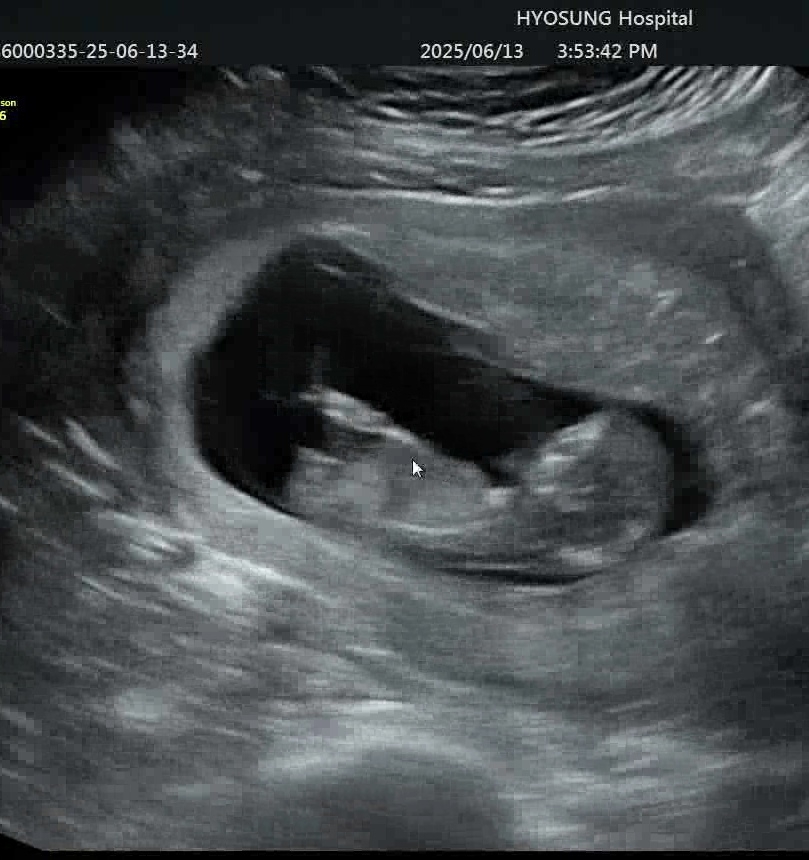

각도법 아시는 분 계신가요?!

다리사이에 튀어나온 것 같아서 아들인가 하고 있는데 각도법은 잘 모르겠어요 ㅠ

딸 한표 드립니다.